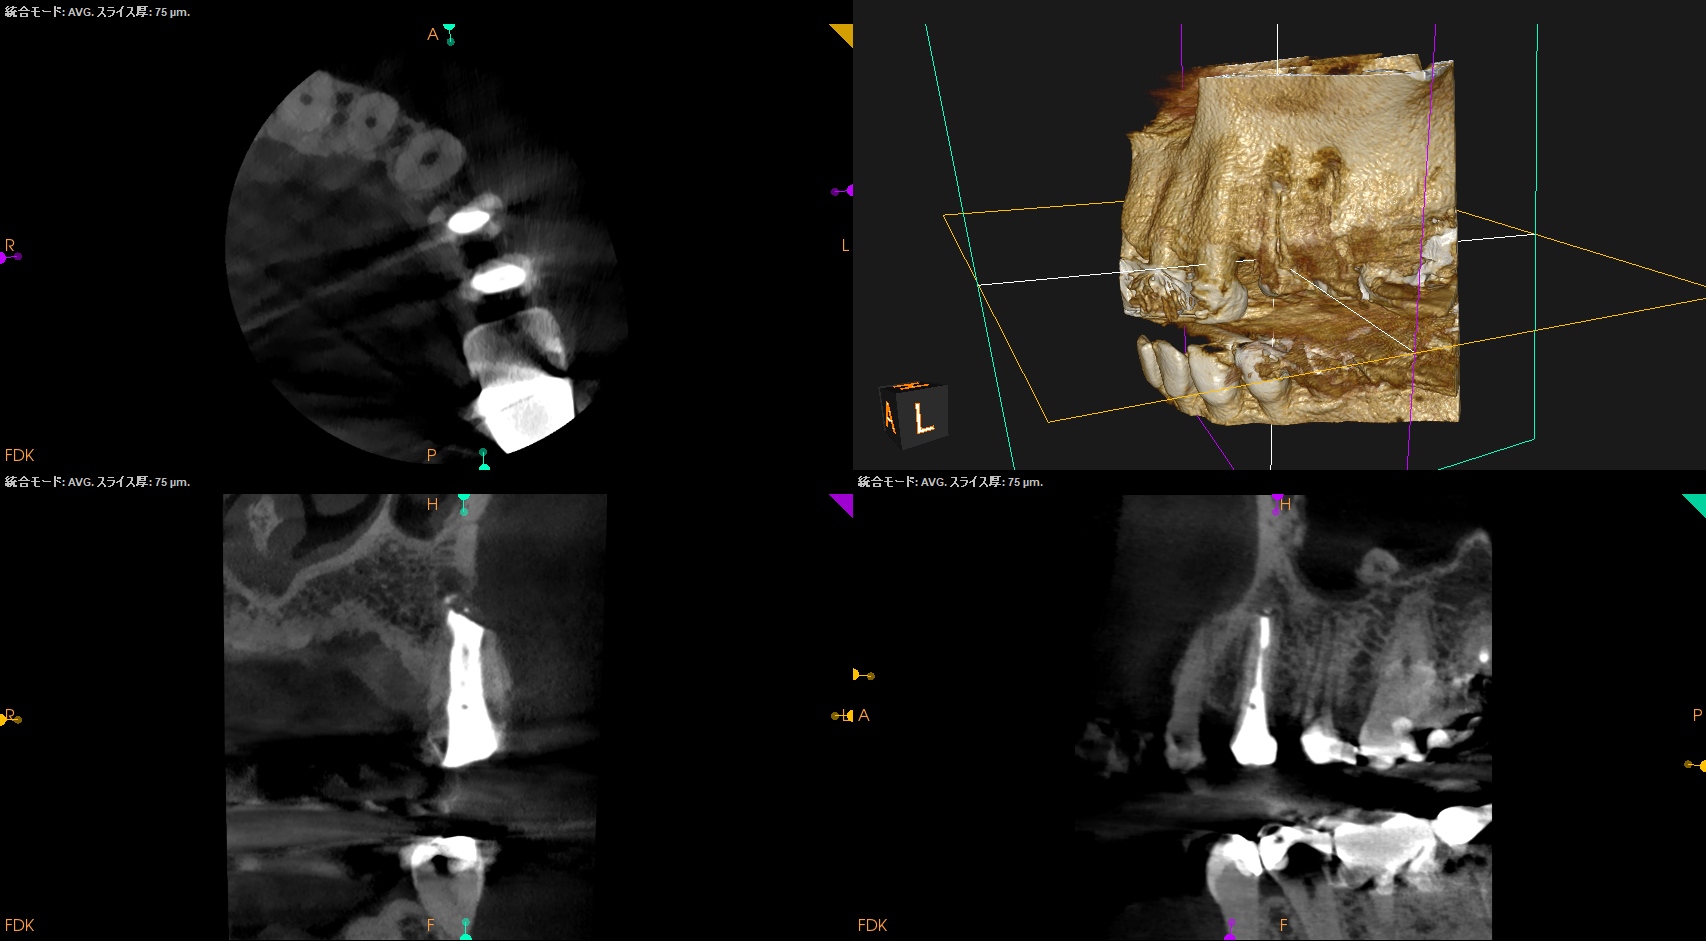

#12,13 Apicoectomy 6M recall(2026.3.31)

#12

#13

術前・直後と比較した。

最終補綴はOKである。